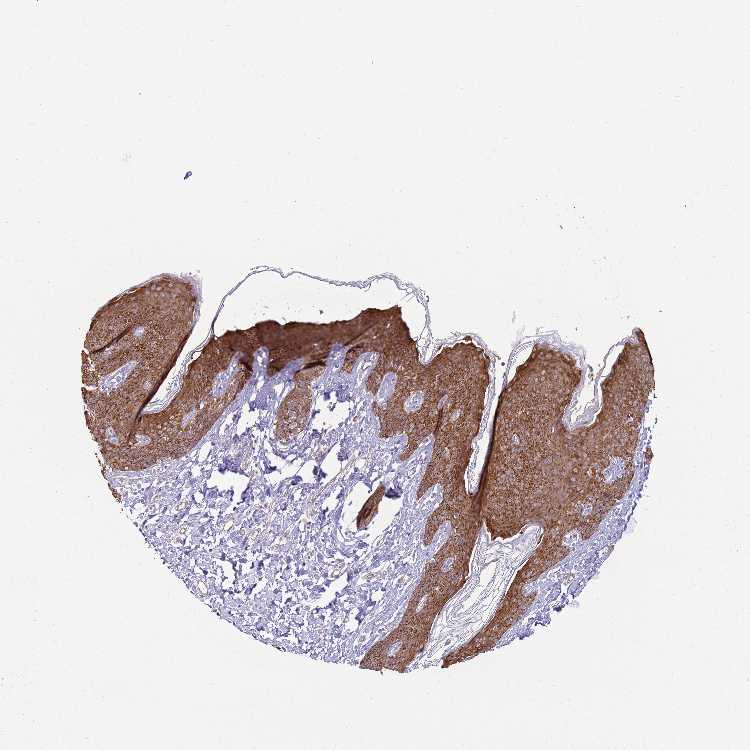

SKIN 1 - Antibody stainingi

Antibody staining in the annotated cell types in the current human tissue is reported as not detected, low, medium, or high, based on conventional immunohistochemistry profiling in selected tissues. This score is based on the combination of the staining intensity and fraction of stained cells.

Each image is clickable and will lead to virtual microscopy that enables deeper exploration of all samples and also displays staining intensity scores, fraction scores and subcellular localization as well as patient and tissue information for each sample.

Antibody HPA000497Antibody CAB004439Antibody CAB047331

Langerhans HighHigh-

Arrector pili muscle cells --Not detected

Cells in basal layer --Medium

Cells in corneal layer --Not detected

Cells in granular layer --Medium

Cells in spinous layer --Medium

Eccrine glands --Medium

Endothelial cells --Low

Extracellular matrix --Not detected

Fibroblasts Not detectedLow-

Fibrohistiocytic cells --Low

Keratinocytes HighHigh-

Langerhans cells --Medium

Lymphocytes --Not detected

Melanocytes MediumHighMedium

Vascular mural cells --Not detected